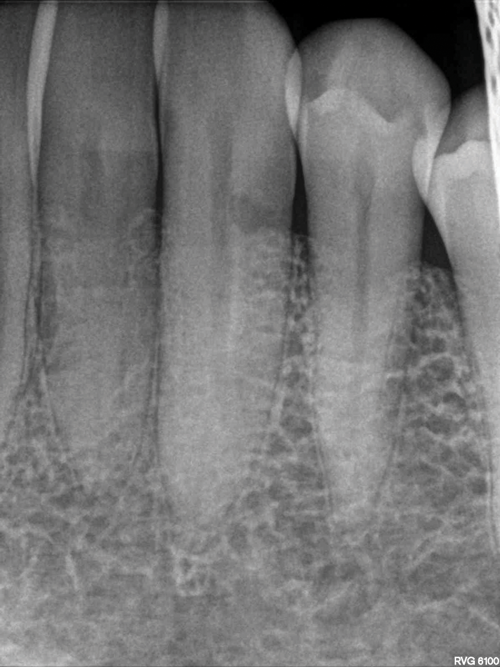

(5.) Close-up clinical and radiographic views of an ECR lesion presenting as a pink spot on the cervical aspect of tooth No. 7.

Figure 5

(6.) Close-up clinical and radiographic views of an ECR lesion presenting as a pink spot on the cervical aspect of tooth No. 7.

Figure 6

Early-stage ECR lesions may not be readily detected on clinical examination. Because the portal of entry normally occurs cervically, ECR lesions are often only palpable subgingivally. Cervical cavitation may be present and can be diagnosed by probing with an explorer-type instrument. When an explorer is used, ECR lesions will feel hard and scratchy like dentin with an irregular surface not like caries lesions, which feel sticky or soft.7,17 The appearance of knife-edge borders around such a cavitation can also help to differentiate ECR from root caries.18 Furthermore, a pink spot or banding may be present at the cervical aspect of the tooth overlying the resorption cavity; however, this finding occurs rarely and may also infrequently be associated with internal root resorption lesions (Figure 5 and Figure 6).19 The pink discoloration results because the granulation tissue of the resorptive defect has become visible through the overlying dental hard tissues. Generally, the gingiva adjacent to ECR lesions can be inflamed and may exhibit easy bleeding on probing due to its vascularity.1,7,14,19 Therefore, the presence of irregular, inflamed, and/or hyperemic gingiva may serve as early indicators of an ECR lesion. More advanced lesions may entrap debris within them, creating a secondary periodontal abscess or caries lesion with associated signs and symptoms.14,6